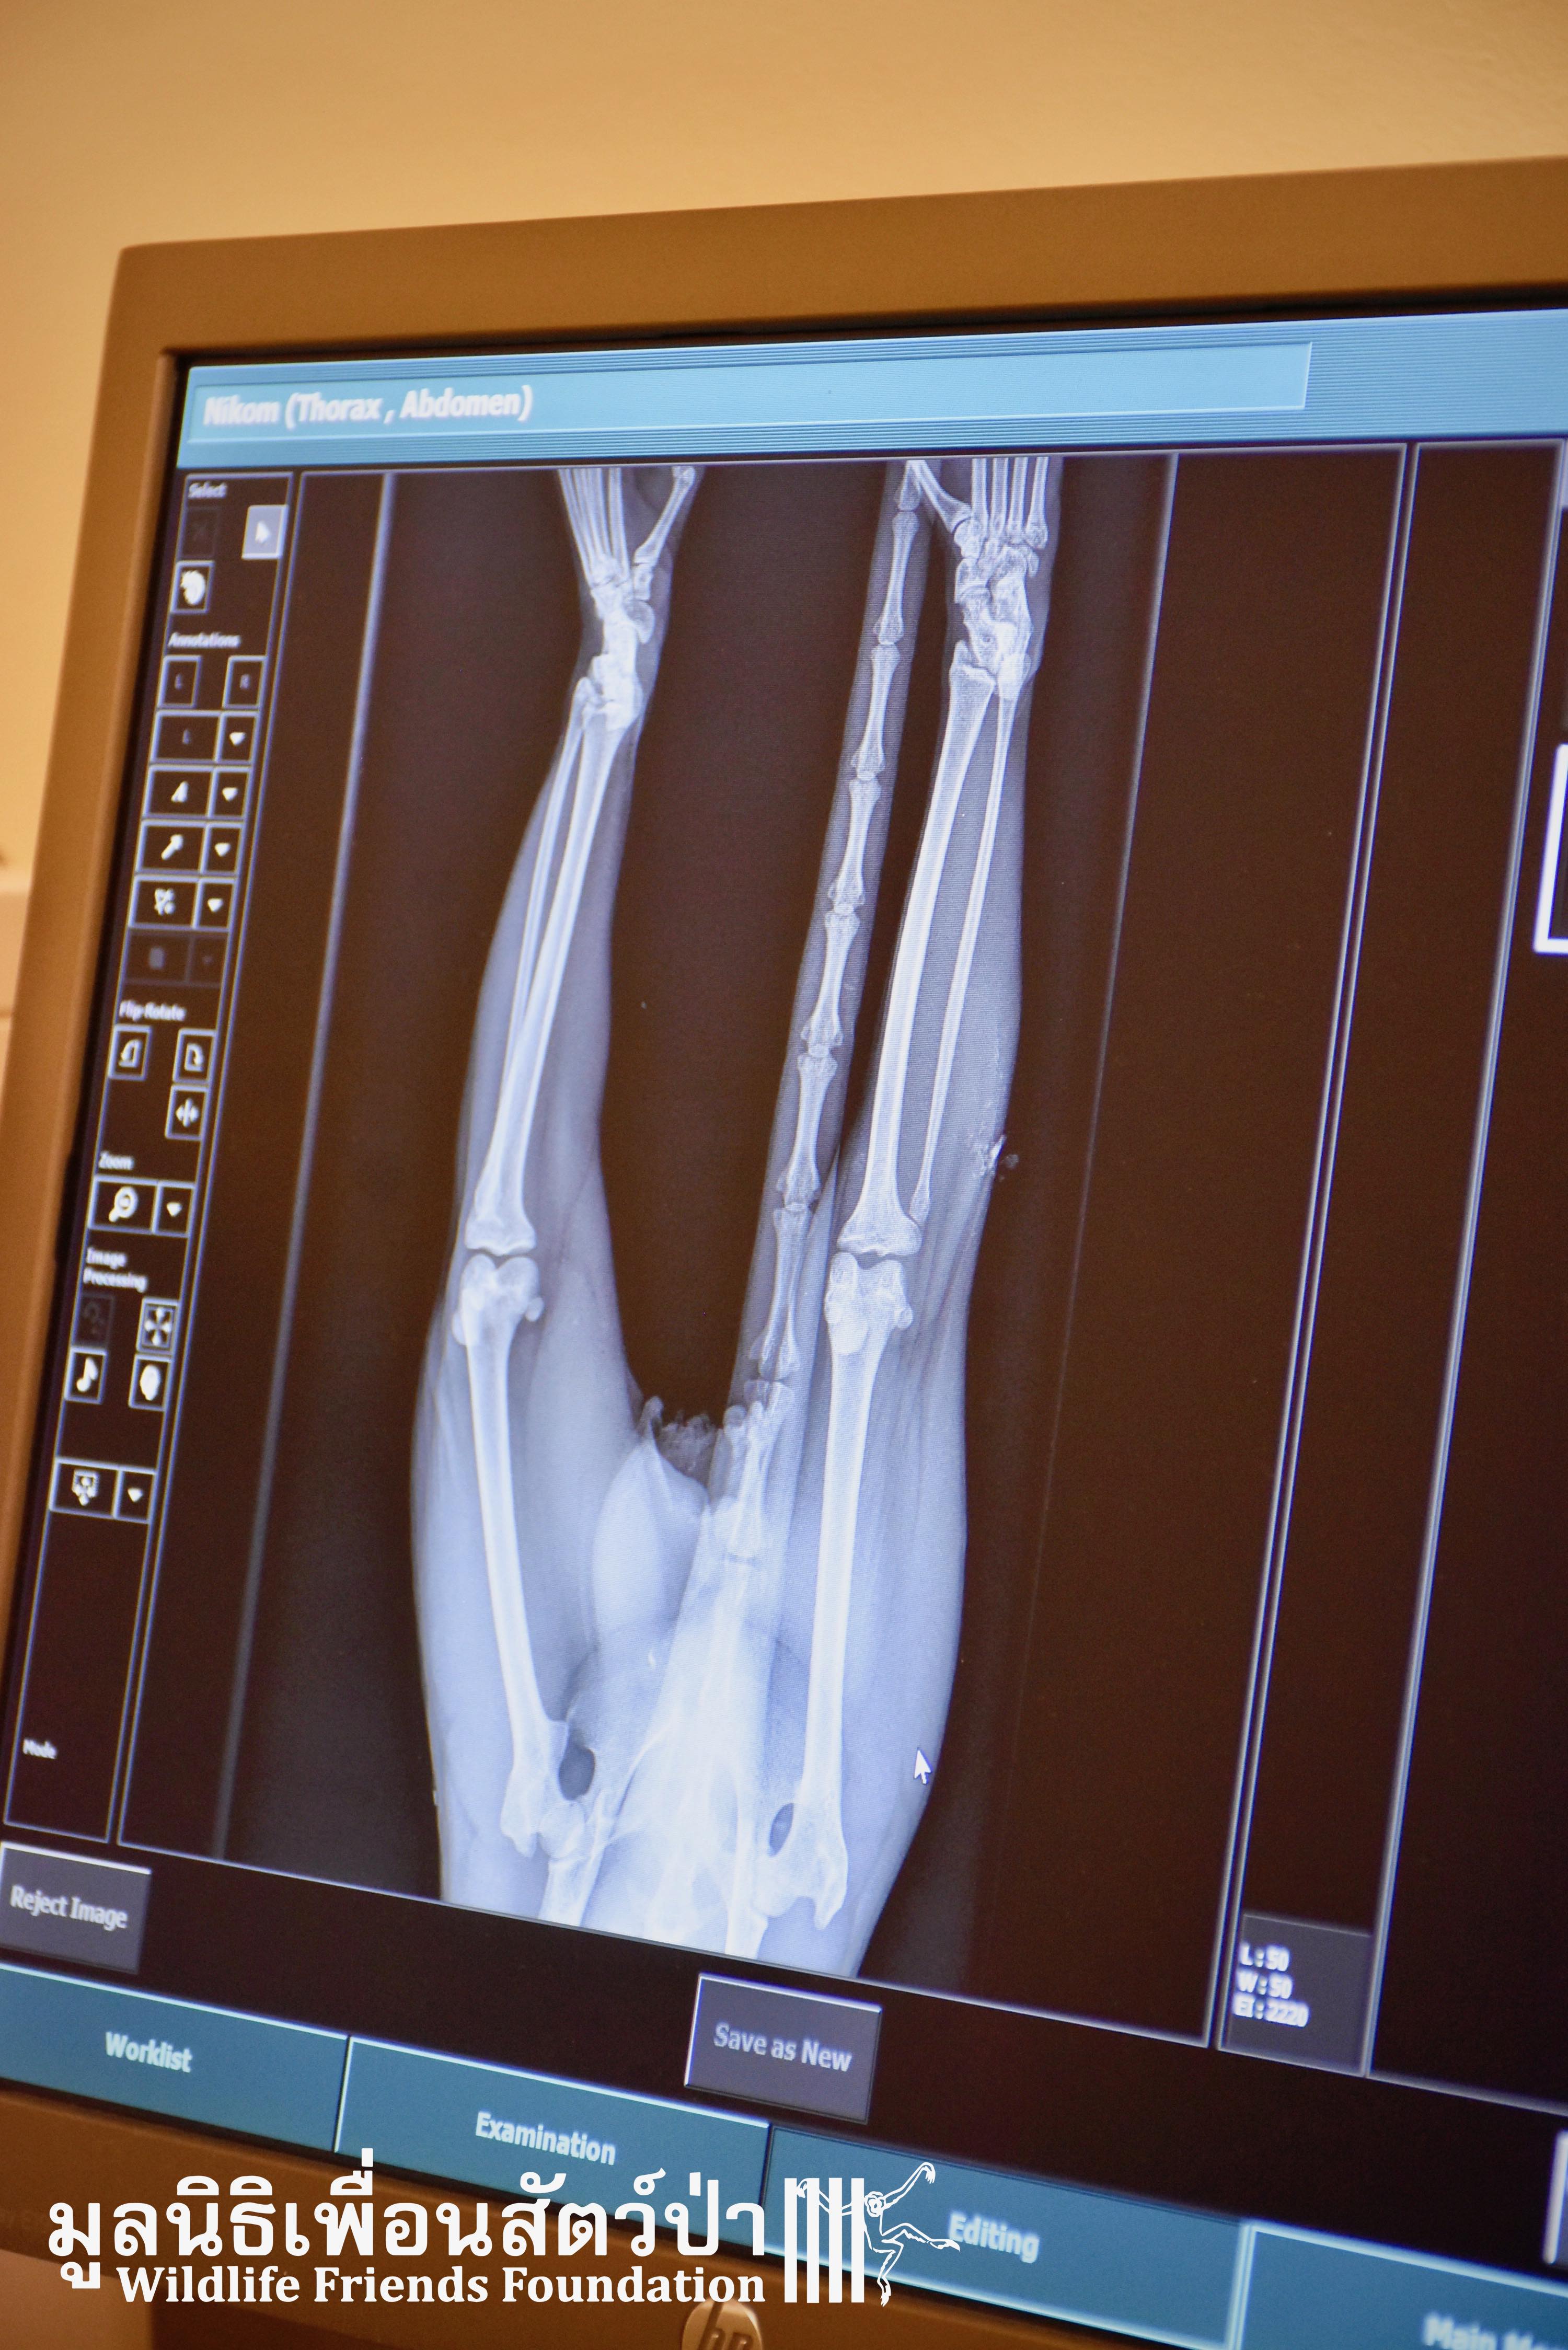

Today we received a call from a compassionate local man who had seen a macaque laying on the ground after being hit by a car. The man sent us photographs of the macaque, the poor monkey was clearly in urgent need of help. The WFFT Wildlife Rescue Team headed out immediately to try and save him. The macaque was next to a temple near Cha-am, approximately 30 minutes away from the WFFT Wildlife Rescue Centre. Upon arrival the team found the adult male long-tailed macaque (Macaca fascicularis) almost motionless. The team loaded him into the rescue vehicle and took him directly to WFFT for an x-ray to determine how severe the injuries were. The results of the x-ray show that nothing was broken. The WFFT Vet Team also checked his health and overall condition. The poor critter, even if without any obvious major injures, will receive the care he deserves and needs till he recovers and be able to return to the wild where he comes from. The health cheek revealed numerous rotten teeth so he will require some dental work before being released back the the wild.